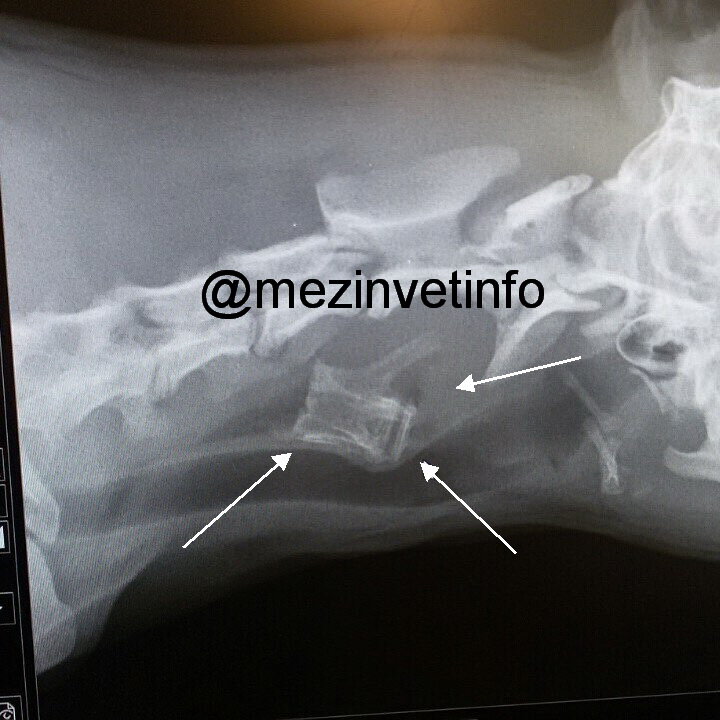

Помощь должна начинаться с диагностики – первоначально проводится рентгенография, на снимке можно четко увидеть инородный предмет и его локализацию.